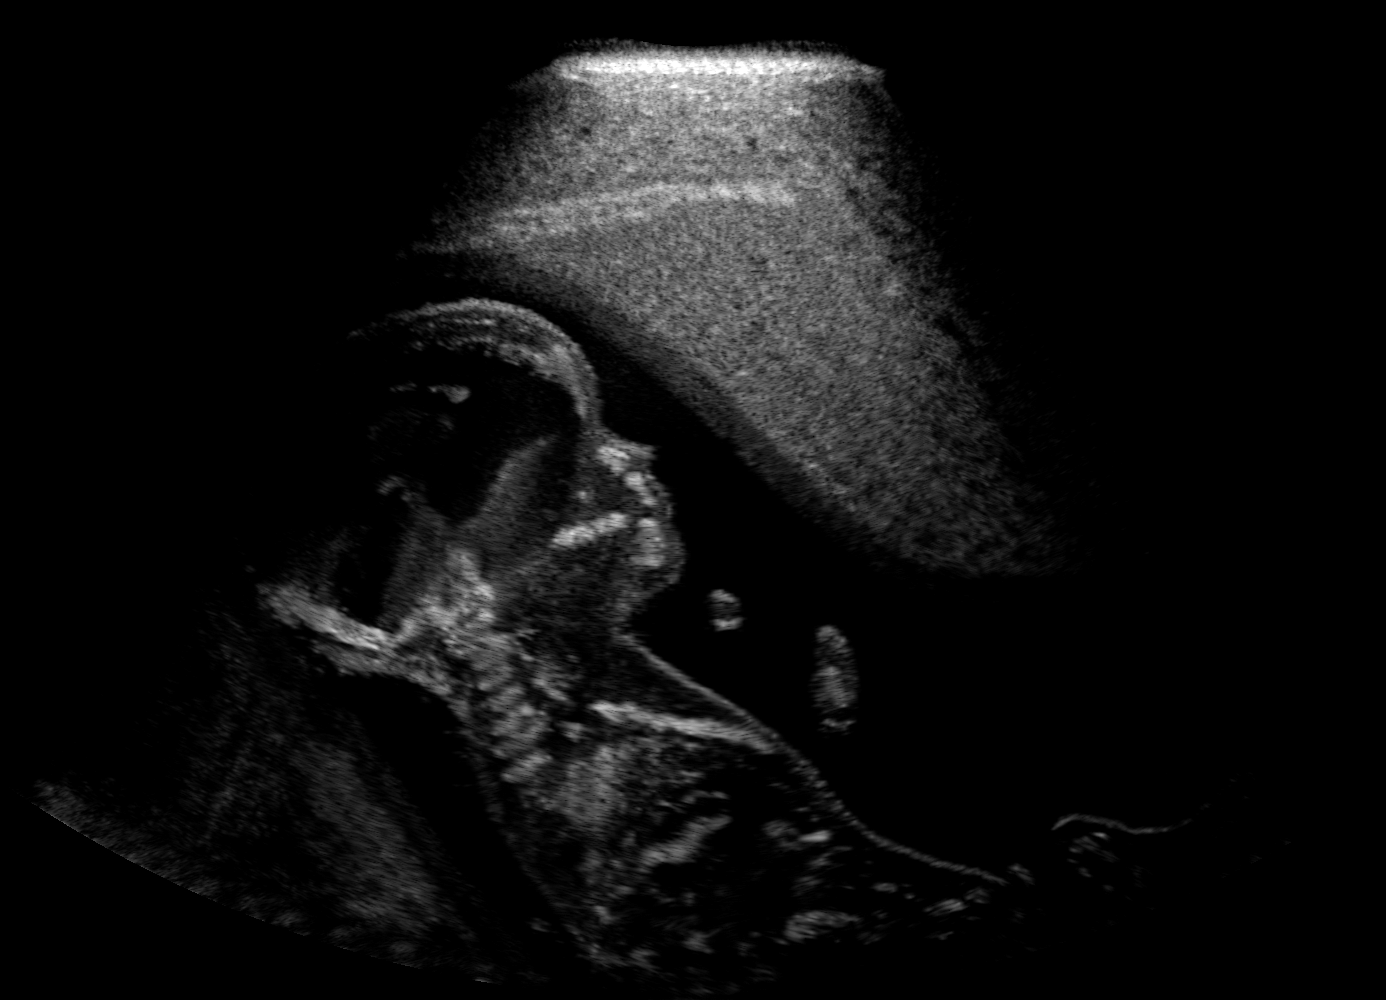

Qualitative evaluation.

Fig. 2 depicts the qualitative results for all the models mentioned above, with arrows pointing at structures relevant to discussion points below. The visual results of the ablated variants of SA2H show substantial quality degradation compared to the full SA2H model, demonstrating the importance of each proposed architectural contribution. Given only segmentation map in the network input, SA2H-att fails to generate acoustic shadows, e.g. those cast by the ribs. Detailed structures such as the cervical vertebrae are blurred out in the SA2H-concat results, which also contain hallucinated structures mainly due to insufficient preservation of input information along the encoding-decoding path. With SA2H-conv, checkerboard artefacts are observed due to the lack of proposed additional stride-1 convolutional layers. SA2H-noise without any explicit noise input is seen to be sub-optimal at generating textural details. The baseline method NSA2H fails to preserve anatomical structures and acoustic shadows in all cases, while the simulated textures also show significant artefacts such as checkerboard patterns. Realism of different simulation aspects may become relevant given different clinical applications and scenarios. For instance, improved structural preservation, e.g. with the hyperechoic bony structures such as the skull and the ribs, of the final model over its ablated variants and NSA2H may prove relevant in fetal head measurements, while the textural improvements facilitating screening fetal organ maturity, e.g. lungs. Compared to the silver-standard model LSA2H with a low-quality rendered image as additional input, SA2H is seen to be on par in structural preservation. Note that shadowing on homogenous regions (e.g. the rib shadowing on the homogenous lung region on the 4th column of Fig. 2) with our proposed method SA2H is represented more faithfully compared to LSA2H, whereas shadows on structurally complex regions (e.g. the skull shadowing around the heart and surrounding tissues on the 3rd column of Fig. 2) are suboptimal with our SA2H. Therefore, one may have to evaluate our method given particular simulation tasks, e.g. its clinical validity for fetal heart exams. However, even with low quality rendered images, LSA2H leads to artificial enhancements of intensities, lack of acoustic shadows, and low-quality textures especially near the probe, for which SA2H yields satisfactory results as illustrated in Fig. 2.

(a) Target

(b) SA2H

(c) SA2H-att

(d) SA2H-concat

(e) SA2H-conv

(f) SA2H-noise

(g) NSA2H

(h) LSA2H